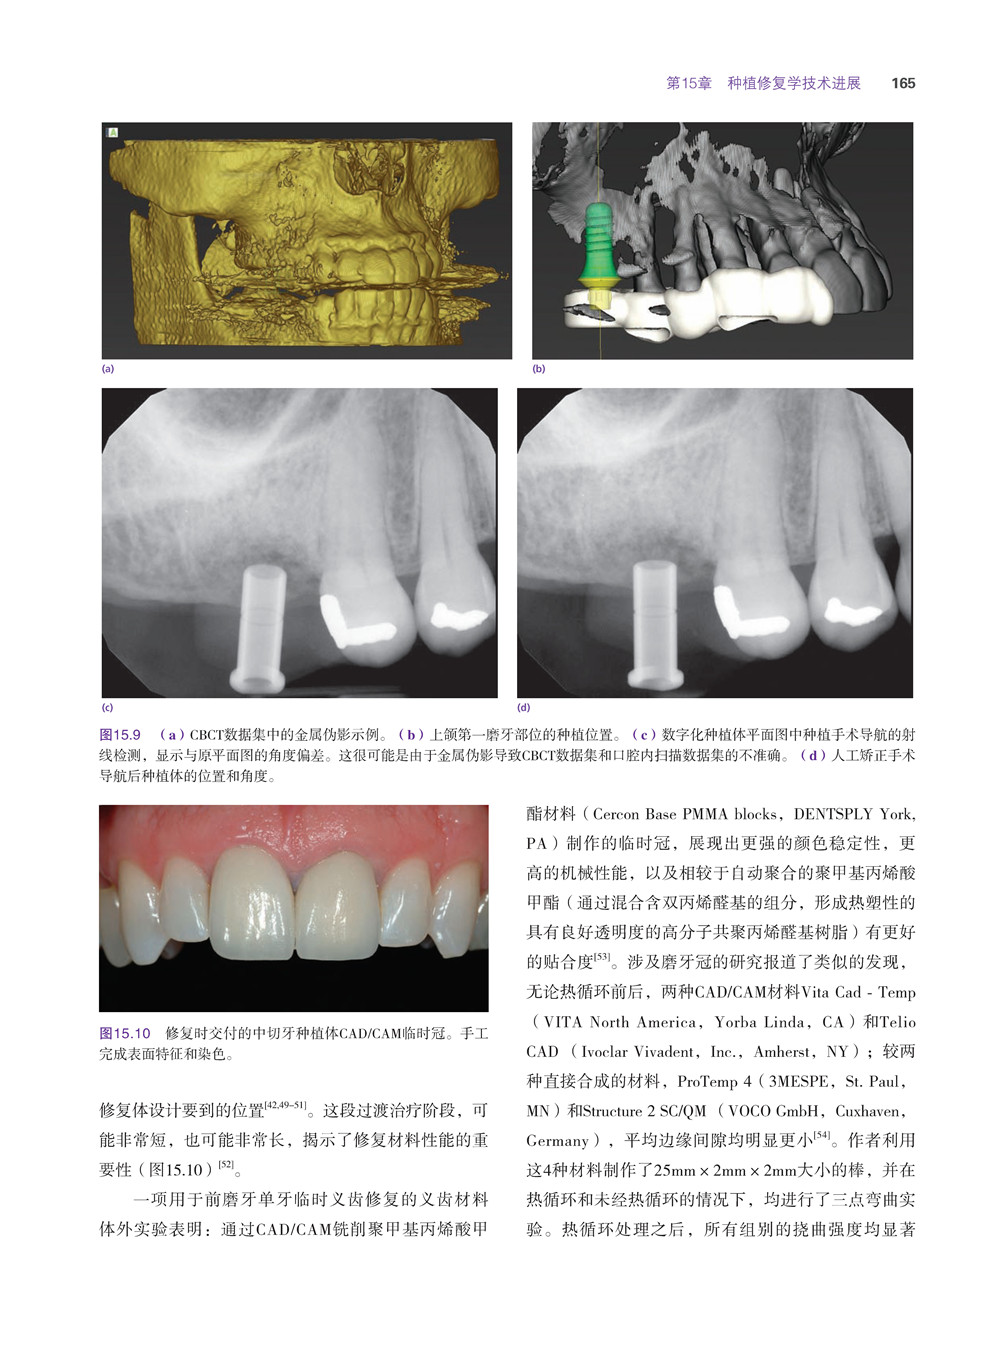

互動式CT 156

互動式電腦軟體157

手術導板157